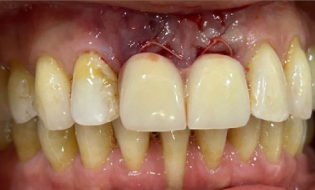

Figure 7

Figure 7 depicts a #9 implant crown.

The patient was especially concerned about the aesthetic of the final restoration and the temporary restoration they would have while waiting for osseointegration.

Figure 9

To assuage their concerns, Dr. Kim affixed the patietn’s natural #9 to #8 and #10 as a temporary after implant placement (Fig 9). As a single central incisor case for such a young and particular patient, had our lab meticulously match the shade and stain during a custom shade appointment to ensure that the patient was happy with the color match.